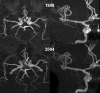

Results: Forty-five saccular aneurysms were detected in 38 patients from 36 families. Most were small (median diameter 3.5 mm) and in the anterior circulation (84%). Median age at diagnosis was 49 years. During cumulative imaging follow-up of 243 years, one de novo UIA was detected and increased in size from 2 to 4.4 mm over 144 months and two UIAs grew from 4.5 to 5.9 mm and 4.7 to 6.2 mm after 69 and 184 months, respectively. Seven patients did not have imaging follow-up. No change was detected in the remaining 28 patients. During cumulative clinical follow-up of 316 years, no aneurysm ruptured. Five patients died from unrelated causes and two were lost to follow-up after 8 and 120 months. Three patients underwent surgical clipping.